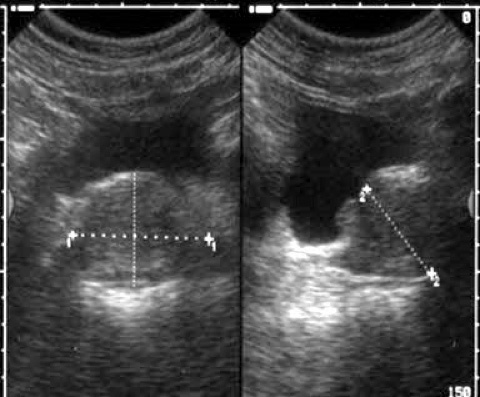

¿Cómo se ve una vejiga con ecografía?

La vejiga normal esta tiene líquido en su interior, se representa como una estructura anecoica con una pared fina, la mejor forma de visualizarla es con moderada repleción, nos permite valorar su pared que debe ser fina de unos 3 mm máximo.

Mediante ecografía se diagnostican:

- tumores vesicales

- divertículos

- litiasis

- infecciones…